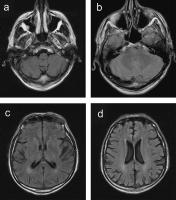

Abbildung 1a-d: MRT 1,5T MRT(Symphony, Siemens). TIRM-Bilder (T2-Wichtung mit Absättigung des Liquor) in axialer Ebene. A: Degeneration im Bereich der Medulla oblongata mit beginnender Atrophie. B: Degeneration im Brückenfuß. C. Diskrete bilaterale Marklagerdefekte periventrikulär im Bereich der Hinterhörner. D: Diskrete bilaterale Marklagerdefekte periventrikulär.